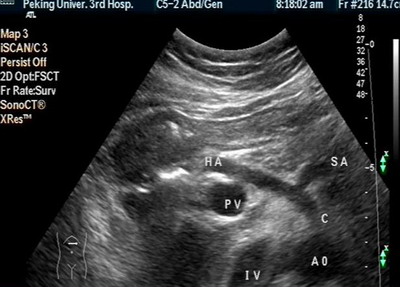

肝脏B超:右肝内及肝尾叶可见巨大强回声结节,9.3×8.8cm,边界欠清,后方回声增强。CDI:肿物周边可见肝动静脉绕行及肿物内门静脉穿行,无明显压迫现象。脾厚5.0cm肋下3.2cm脾门处脾静脉宽0.8cm